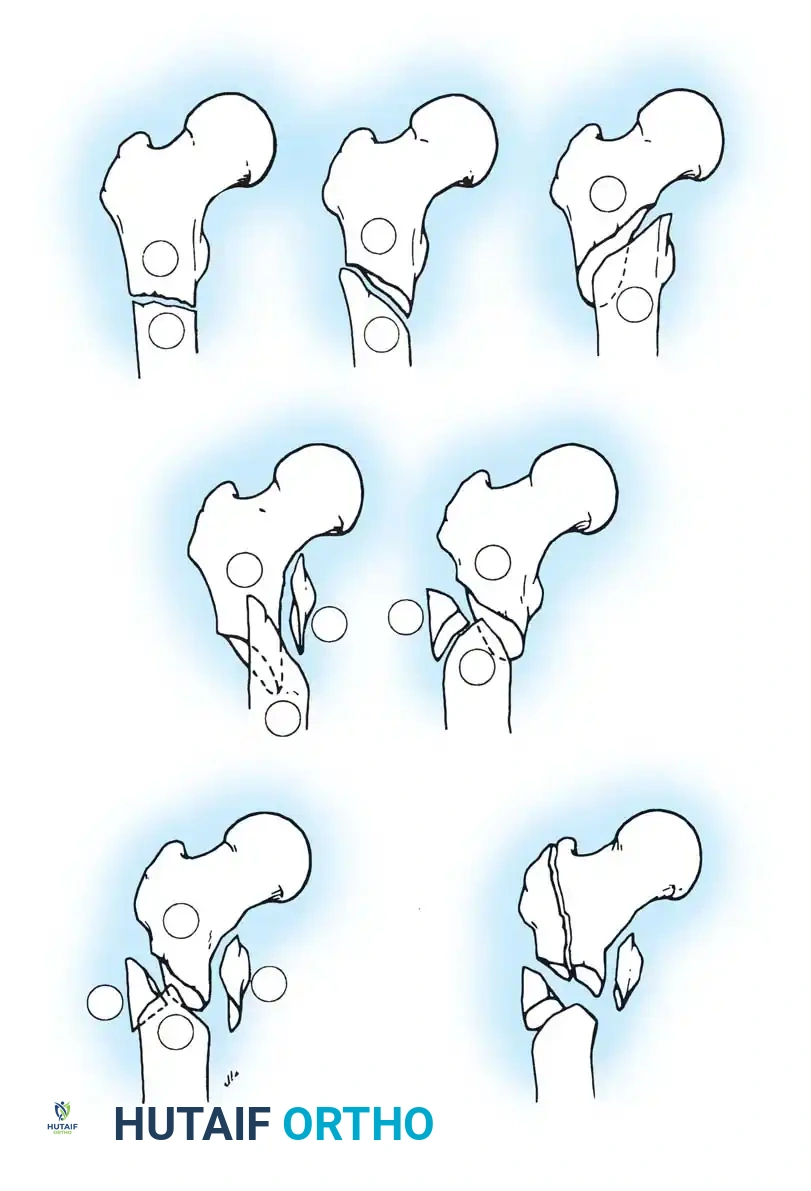

Fig. 52-2: Boyd and Griffin Classification of trochanteric fractures. Types 1 and 2 represent relatively simple patterns, while Types 3 and 4 involve subtrochanteric extension and multi-planar comminution.

- Type 1: Non-comminuted fractures extending along the intertrochanteric line. Simple to reduce and highly stable.

- Type 2: Comminuted fractures along the intertrochanteric line. Reduction is more challenging due to cortical comminution.

- Type 3: Fractures with a subtrochanteric extension. These are inherently unstable and difficult to manage.

- Type 4: Complex fractures involving the trochanteric region and proximal shaft in at least two planes (sagittal and coronal).

Fig. 52-4: AO Classification of trochanteric fractures. A1 (simple), A2 (comminuted), and A3 (reverse obliquity/transverse).

- 31-A1: Simple, two-part fractures (Stable).

- 31-A2: Comminuted fractures with posteromedial fragmentation (Unstable).

- 31-A3: Reverse obliquity or transverse fractures extending into the lateral cortex (Highly Unstable).